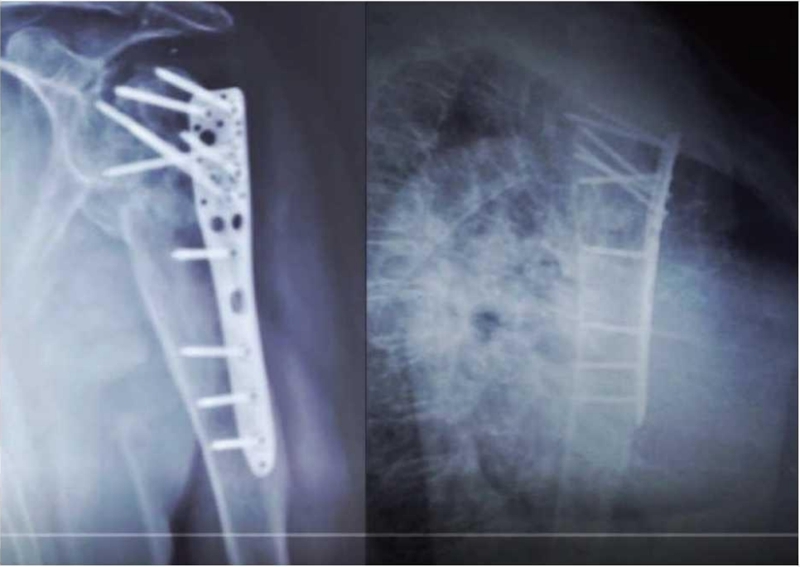

该例患者为65岁肱骨近端骨折术后患者,肩关节功能严重受损(图11~13)。

图11 肩关节X线片示肱骨近端骨折术后肱骨大、小结节吸收

图12 手绘图示肱骨近端骨折术后大、小结节缺失

患者右肩关节疼痛严重,功能受限,术前评估及分析后决定行翻修手术,即取出内固定后一期行反肩置换手术。术中显露后发现右肱骨近端大结节吸收缺损,肩袖巨大撕裂(图14)。

图14 右肱骨近端内固定取出术后大结节坏死吸收,肩袖巨大撕裂且无法重建